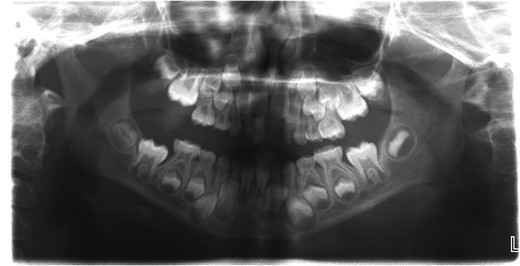

A 6-year-old girl presented to the Emergency Department with a suspected mandibular dislocation after falling off her scooter. She was previously fit and well with no significant medical history. She had complete restriction of all mandibular movements and trismus. The dental occlusion demonstrated a cross-bite with all the posterior teeth in contact and a mandibular asymmetry with the chin significantly deviated to the left side. Radiographic investigations (orthopantomogram (OPG) and postero-anterior (PA) mandible images) were performed but confirmation of the dislocation could not be determined on these views (Fig. 1). Consequently, a computerized tomography (CT) scan was performed that confirmed significant displacement of the condyle anteriorly and superiorly into the infratemporal fossa (Fig. 2). In addition calcification of the lateral and medial pterygoid muscles was noted on the affected side indicating chronic nature of the condition. Discussion with the patient’s general dental practitioner (GDP) revealed that the patient had a pre-existing dental malocclusion comprising of a cross-bite and mandibular asymmetry and this was also corroborated by a photograph taken well before the scooter accident. On this evidence it was therefore presumed that the condyle had been dislocated for many months or years and the scooter accident had only highlighted this. There were no other traumatic events of note in the history. The TMJ could not be convincingly reduced via a Hippocratic manoeuvre under a short general anaesthetic despite several attempts. In order to re-image the TMJ a magnetic resonance imaging scan was performed to prevent additional irradiation. This scan confirmed that the TMJ was still dislocated and had not been reduced. Due to the unsuccessful closed reduction, it was decided to perform an open reduction via a Risdon incision. When reduction with traction wires at the mandibular angle failed a bone hook was placed into the sigmoid notch and the dislocation was reduced using a fair degree of force.

Orthopantomogram (OPG) of the patient with longstanding dislocation.